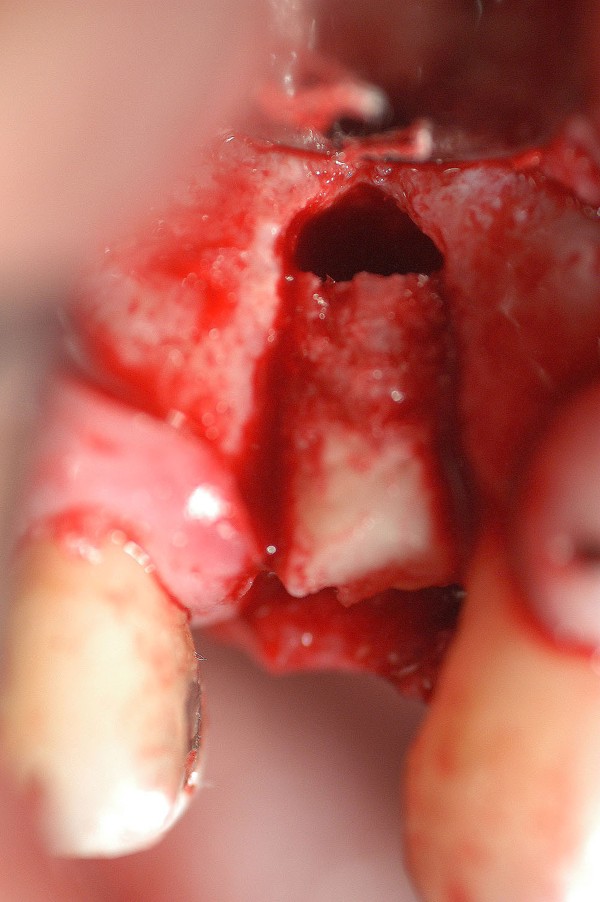

EFECTOS DEL TABAQUISMO CRÓNICO SOBRE LA IRRIGACIÓN ÓSEA TERMINAL. Es por todos conocido el efecto deletéreo que el uso del tabaco provoca sobre la irrigación terminal de mucosas y hueso. Su uso además produce un aumento en la frecuencia cardíaca y la presión arterial, volumen sistólico y gasto cardíaco, a sí como del flujo sanguíneo coronario. vasoconstricción cutánea con una disminución asociada de la temperatura cutánea, y un aumento del flujo sanguíneo muscular. Muchas veces , la intención terapéutica excede los propósitos del paciente de alejarse del tabaco , y se abordan soluciones que terminan en fracasos. Paciente mujer de 53 años de edad, carente de enfermedades, fumadora de dos paquetes diarios de cigarrillos, bruxómana. Se presenta con dolores en la zona de un premolar superior, que porta corona de porcelana sobre un perno colado de oro, con su correspondiente tratamiento de conducto, realizados en mi consulta, veinte años atrás. Se procede a extraer la pieza dentaria, y se observa la pérdida total de la tabla vestibular. Transcurridos seis(6) meses, tiempo mas que suficiente para la conveniente formación de nuevo hueso, se procede a implantar, observándose entonces, que no solo no existía osteogénesis, sino que además se había reabsorbido también la tabla palatina y parte del hueso periférico al canino. En un intento heroico de resolver el caso, se procede a tomar un injerto autólogo de la zona del trígono retro molar, y fijarlo mediante micro tornillo de síntesis en la zona afectada, realizando perforaciones alrededor del lecho quirúrgico a fin de aumentar la irrigación por estímulo traumático del hueso periférico Se vuelve a cubrir con Bioss y membrana Bio Guide, y se sutura convenientemente. Al cabo de otras dos semanas, se expone la porción caudal del injerto, acusando evidentes signos de falta de irrigación. Se retira del lecho receptor, se curetéa y se deja cicatrizar por segunda intención. El caso se encuentra a la espera de solución protética fija. FIG16

FIG2

LA FIG 11 CORRESPONDE A LA «ZONA DADORA» DEL INJERTO QUE FUE TOMADO DE LA ZONA RETROMOLAR.

LA FIG 12 ES EN EL MOMENTO DE LA INSTALACIÓN DE DICHO INJERTO

LA FIG 13 CORRSPONDE A LA FIJACIÓN DEL MISMO MEDIANTE UN MICROTORNILLO DE FIJACIÓN, Y LA 14 AL CUBRIMIENTO DEL TODO MEDIANTE HUESO BOVINO MARCA BIOS.